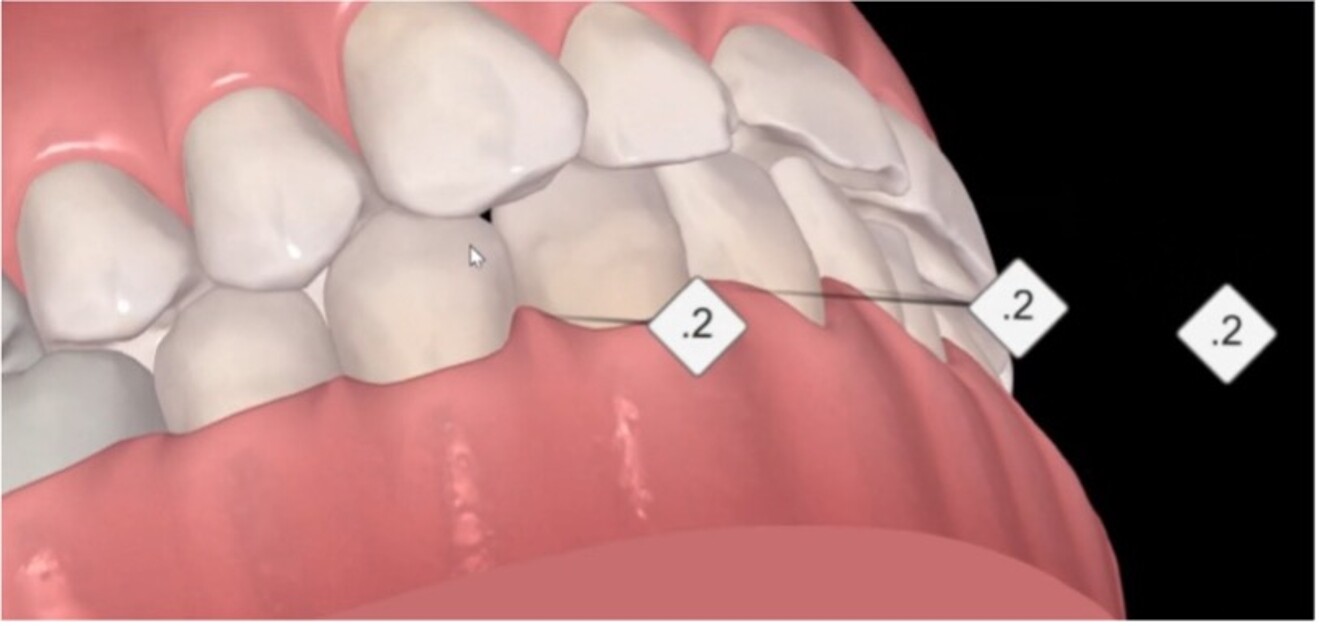

Figs. 3a & b: Side-by-side lingual view of the pre- (a) and post-alignment ClinCheck images (b) with restorative overlay displaying orthodontic space creation for the restorative and prosthodontic phase of treatment.

Space creation is a central factor in pre-restorative orthodontic. Treatment planning tools such as Invisalign ClinCheck (Align Technology) can simulate tooth positions, providing valuable insight into final orthodontic outcomes. Similarly, smile design or restorative overlay software allows for consideration of ideal restorative size, shape and of position. By overlaying these two digital visualisations, clinicians can better conceptualise how much space is required for the restorative phase.

The creation of space includes adjustments in the mesiodistal, vertical and buccolingual planes. Achieving space across these multiple planes, often with a combination of tooth movements, creates a more ideal pre-restorative position. For example, vertical correction helps level gingival margins and improves vertical restorative volumes, both of which are key to achieving symmetrical, additive-focused dentistry.